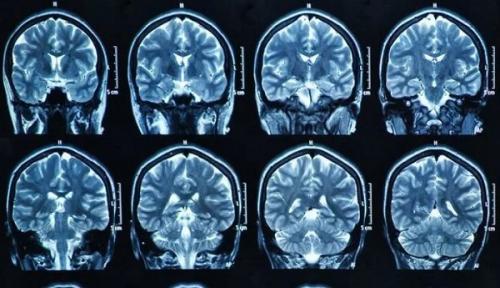

Микроинсульт на МРТ. Инсульт на МРТ головного мозга

Инсульт представляет собой острое нарушение мозгового кровообращения. Это неотложное состояние развивается стремительно, сопровождается группой симптомов. В их числе:

В результате течения патологического процесса наблюдается очаговое или диффузное, распределенное поражение мозговой ткани. Заболевание подразделяется на два типа:

- Ишемический инсульт сопровождается нарушением питания тканей ЦНС без признаков нарушения анатомической целостности сосудов.

- Геморрагическая форма — сопровождается разрывом сосудов головного мозга, кровоизлиянием в ткани ЦНС.

Магнитно-резонансная томография представляет собой экстренный способ диагностики нарушения мозгового кровотока. Инсульт на МРТ головного мозга виден в первые же сутки после развития патологического процесса. Но для его выявления может потребоваться модификация метода, а не стандартная обзорная томография. МРТ после инсульта также проводится. Томография показывает степень нарушения кровотока, поражения тканей. Все же есть отдельные нюансы проведения магнитно-резонансной томографии при подозрениях на инсульт.

Какое МРТ делать после инсульта?

Томография при инсульте проводится двумя основными способами.

- Первый — стандартная обзорная томография. Долгие годы она была единственным вариантом диагностики патологического процесса. Благодаря нейровизуализации врачи получают возможность оценить состояние головного мозга, его отдельных участков. Области ишемии или геморрагии хорошо видны. Можно оценить степень нарушения, спрогнозировать вероятный исход, разработать метод грамотной терапии в определенном клиническом случае. У методики есть минус — она показывает состояние церебральных структур, выявляет патологический процесс только спустя как минимум сутки от развития расстройства. Для экстренного определения нарушения она не годится. Нужна более чувствительная методика.

- Второй — диффузионная МРТ. Эта модификация классического способа должна установить диагноз в первые 24 часа после наступления поражения церебральных структур. Томографический способ основан на способности МРТ-аппарата регистрировать особенности движения молекул воды в нервных тканях. Благодаря чему врачи получают возможность выявить область нарушения работы ЦНС, степень поражения в острейшем периоде.